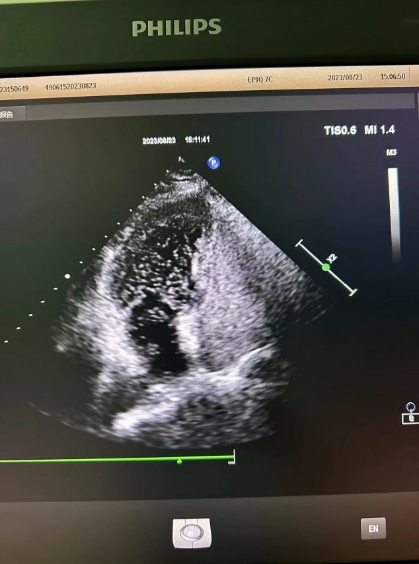

超声心动图检查发现可能存在卵圆孔未闭,经心内科会诊,详细询问病情、仔细了解病史后,为进一步明确诊治,决定为患者进行右心声学造影检查。右心声学造影是一项无创、便捷的超声检查技术,医护人员首先在患者胳臂上建立一个静脉通路,然后把含有微小气泡的振荡生理盐水注入患者体内,同时将超声探头放在患者心前区,借助超声检查设备,观察进入人体心腔的微小气泡运动情况。

患者检查后果然发现了异常,从屏幕上可以清晰看到,患者左心房内很快出现了大量微小气泡,这说明该患者的心脏存在着房水平由右向左的分流,提示有先天性卵圆孔未闭!根据这一检查结果与患者及家属沟通后,心内科为其进行了卵圆孔未闭封堵术,最终改善了患者多年来的头晕头痛症状。